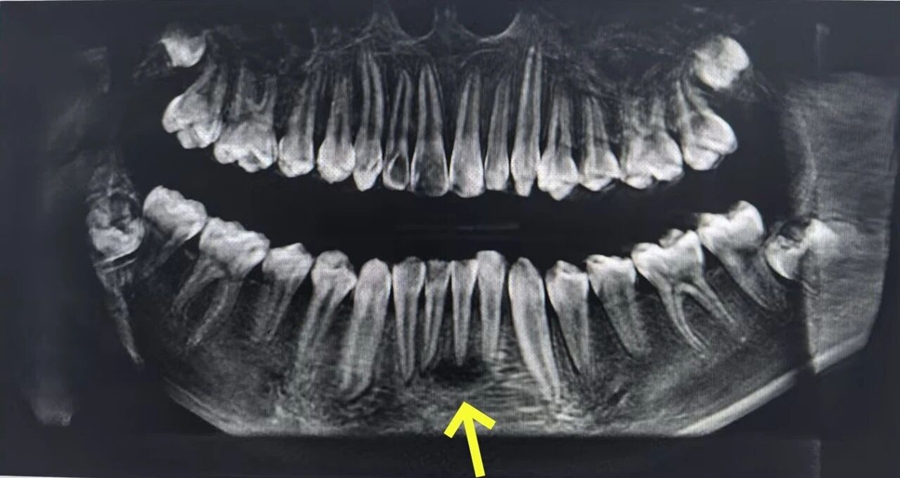

CBCT(口腔錐形束計(jì)算機(jī)斷層掃描檢查)提示根尖周大面積低密度影,結(jié)合牙髓電活力測(cè)試,最終診斷為31、32急性根尖周炎、牙周-牙髓聯(lián)合病變!